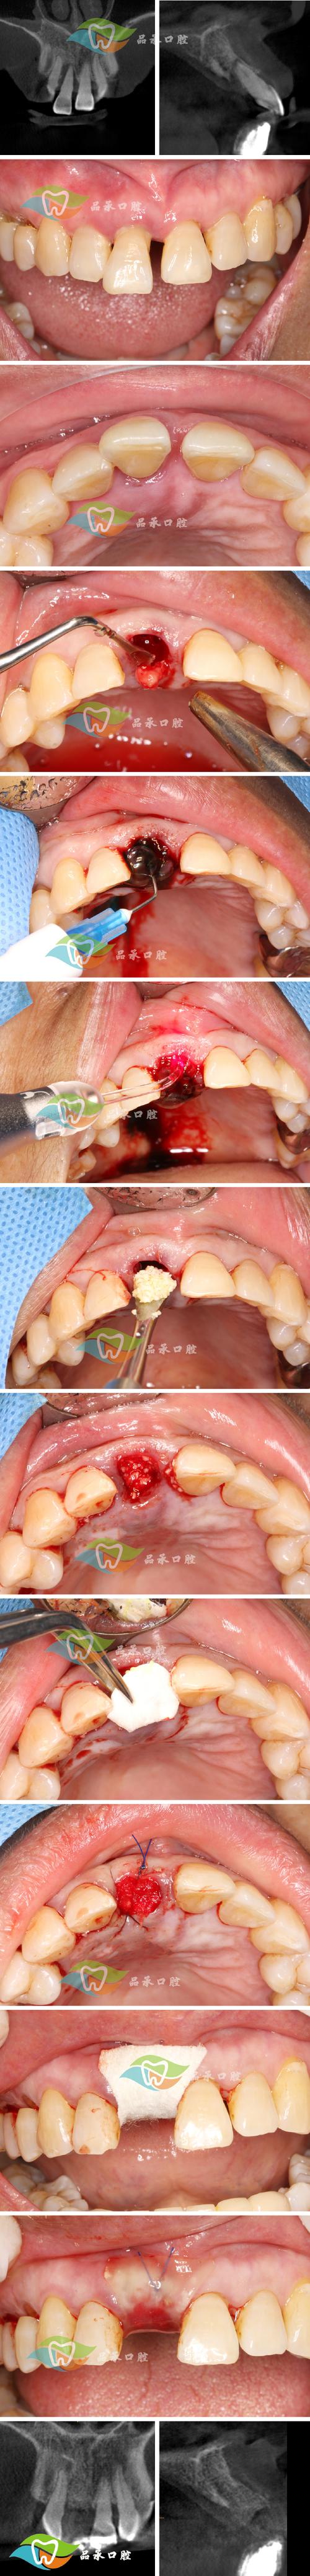

植骨材料暴露

若术中缝合不严密、术后咀嚼硬物或外力撞击,可能导致植骨材料(尤其是颗粒状材料)穿透黏膜暴露于口腔,暴露的材料表面易附着菌斑,形成白色覆盖物,同时可引发局部炎症,导致黏膜发白、疼痛。 -